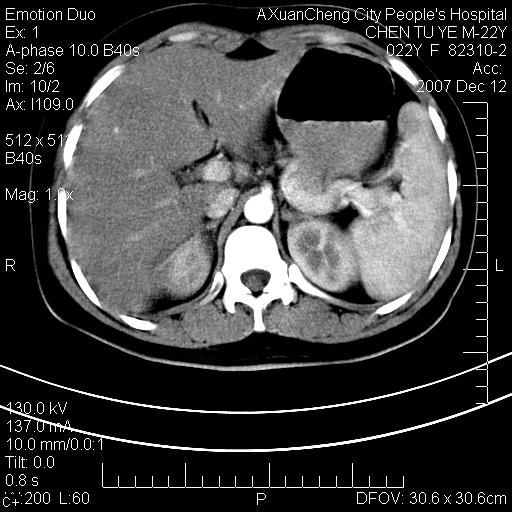

超声提示肝右前叶占位,约2.5cm.

各位战友看看病灶在什么地方,可是右前叶进肝裂部低密度影,平扫ct值约10以下,增强后增高明显

1 脾大,慢性肝损伤. 2 肝脏脂肪侵润.  3 你所指的部位疑点,我没看出有问题.

脂肪肝.楼主所指部位不考虑异常,为肝圆韧带影.

不均匀脂肪浸润,版主所说的病灶为肝园韧带服着点。

考虑肝圆韧带。